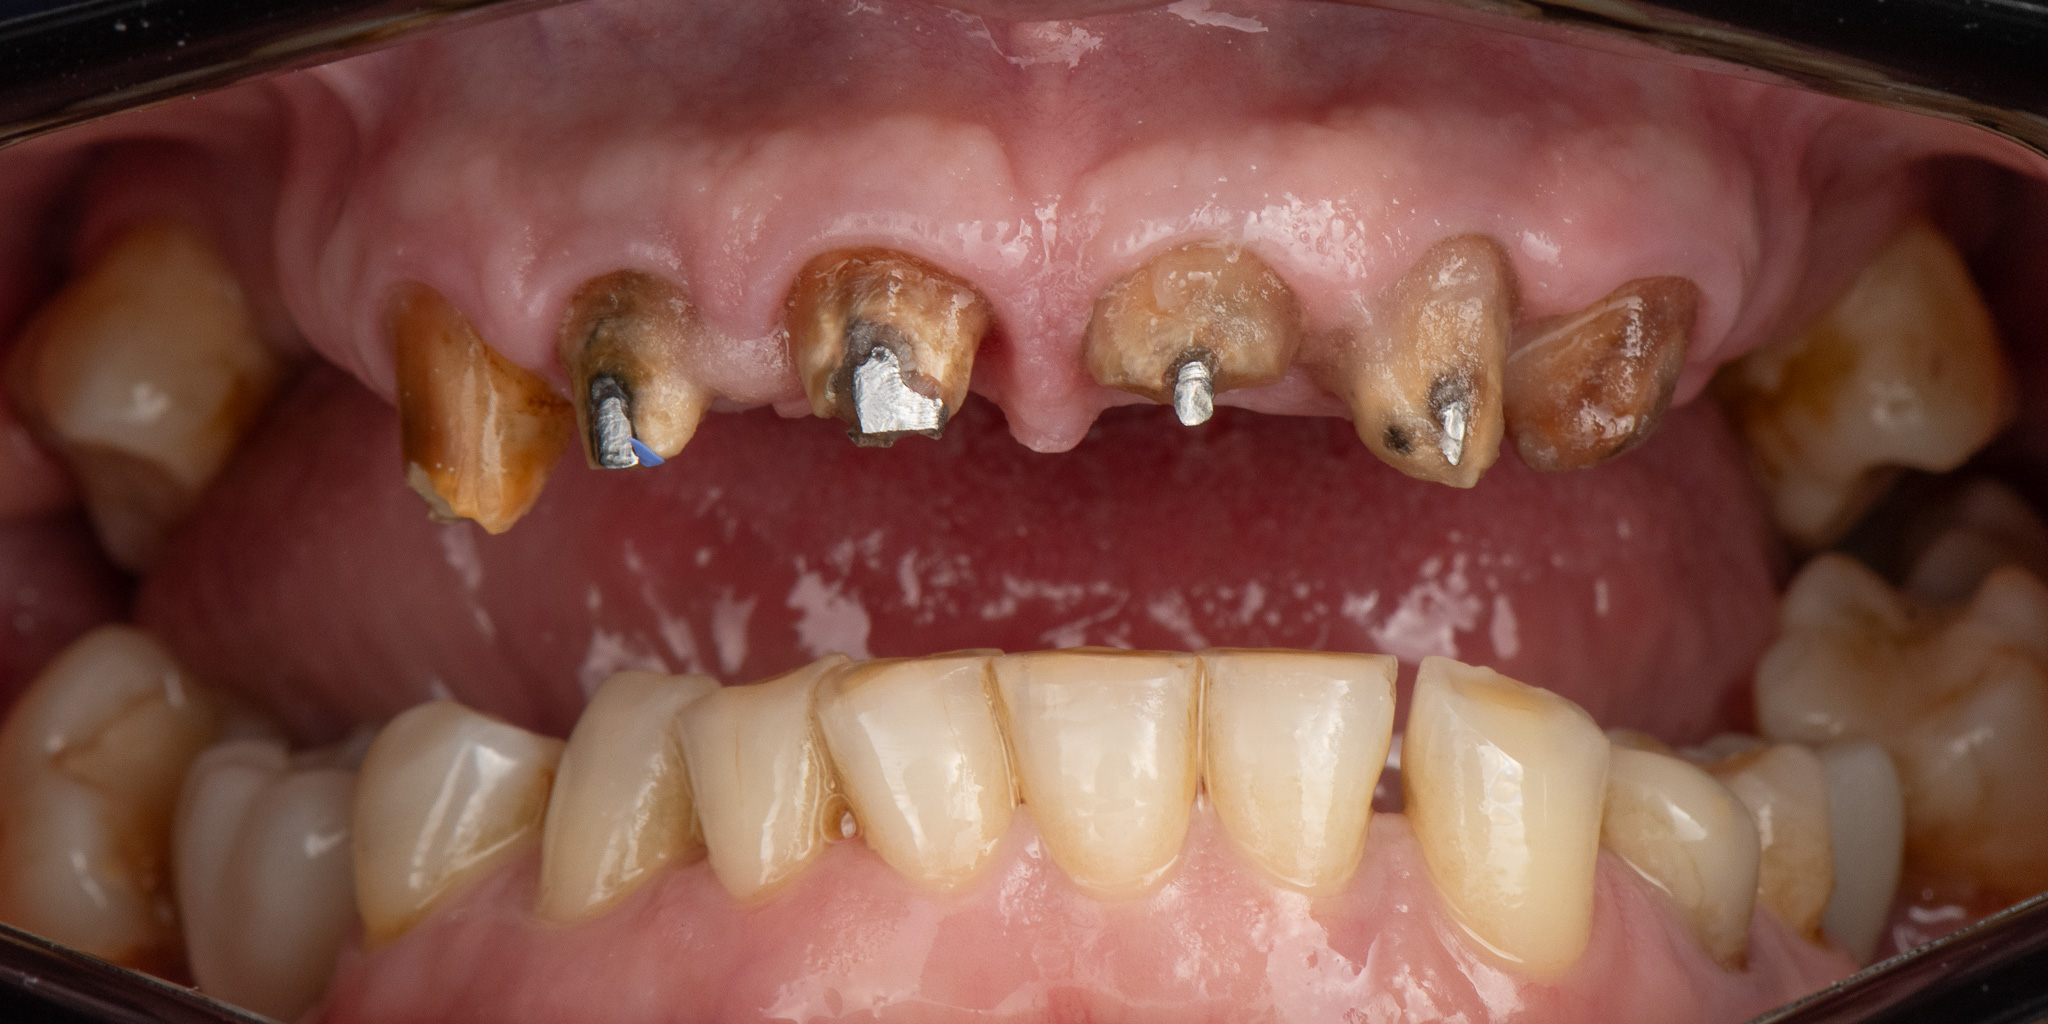

Pacjent zgłosił się ze zużytym tymczasowym mostem protetycznym

Zaplanowane leczenie obejmowało wykonanie nowych koron ceramicznych na podbudowie metalowej oraz protez szkieletowych górnej i dolnej.